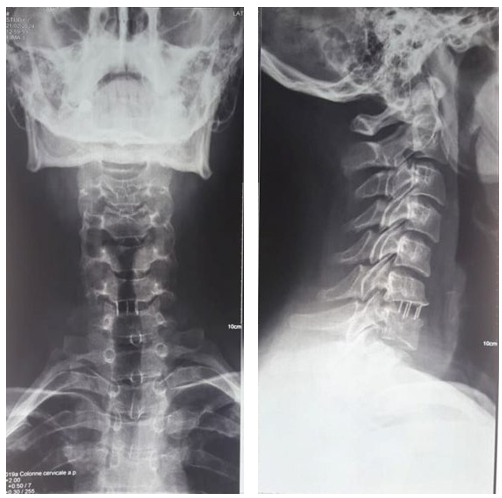

ENT examination with laryngoscopy revealed no lesions or swelling in the nasopharynx, hypopharynx, or larynx. Cervical radiographs showed migration of the cervical cage at the C6-C7 level (Figure 1). The patient had a surgical removal of the migration cage, which was then replaced with a new one (Figure 2). The patient did well postoperatively, remained in the hospital for a few days for immediate postoperative follow-up, and was discharged home asymptomatic a week later.

Figure 1: Cervical Spine X-ray showing Migration of C6C7 Arthrodesis Material

Figure 2: Cervical Spine X-ray showing Replacement of C6C7 Arthrodesis Material